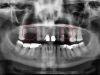

• до синус-лифтинга

• после синус-лифтинга

• после установки имплантатов в верхнюю челюсть

• коронки установленные на имплантаты